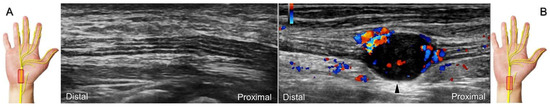

Chronic irritation may lead to the formation of a neuroma, which can occasionally be detected through US imaging (Figure 31). Using the in-plane approach in short-axis view (Figure 32, Video S4), hydrodissection of the entrapped nerves can be performed after identifying the palmar common digital artery and flexor digitorum superficialis/profundus tendons.

Figure 31. Sonographic imaging of the neuroma of the palmar proper digital nerve in short-axis (A) and long-axis (B) views. White arrowheads: normal segments of the palmar proper digital nerve; black arrowhead: neuroma. FPL: flexor pollicis longus tendon.